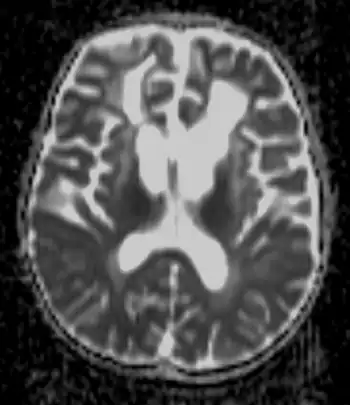

![]() |

Detecting the signs of Alexander disease is possible with magnetic resonance imaging (MRI), which looks for specific changes in the brain that may be tell-tale signs for the disease.[11][12] It is even possible to detect adult-onset Alexander disease with MRI.[10] Alexander disease may also be revealed by genetic testing for its known cause.[13][14] A rough diagnosis may also be made through revealing of clinical symptoms, including enlarged head size, along with radiological studies, and negative tests for other leukodystrophies.[8]